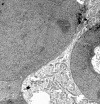

Methods: Use of a novel digital confocal laser scanning microscope, a combination of the Heidelberg retina tomograph (HRT II) and the Rostock cornea module. Exchange of aqueous humour solution from domestic pigs against glycerol/water solutions (refractive indices eta = 1.337-1.47). Transelectron microscopy of endothelial and epithelial cell morphology.

Results: Under the terms of variable refractive indices no differences were observed for general imaging of endothelium. Bright cells were bordered by dark cell membranes in all experiments. Electron microscopy of endothelium and epithelium revealed differences in intracellular and cell membrane structure of both cell types.

Conclusion: Source of specific confocal optical behaviour of endothelium does not come from interface conditions to aqueous humour, but may result from intracellular variations and ultrastructure of cell membranes.